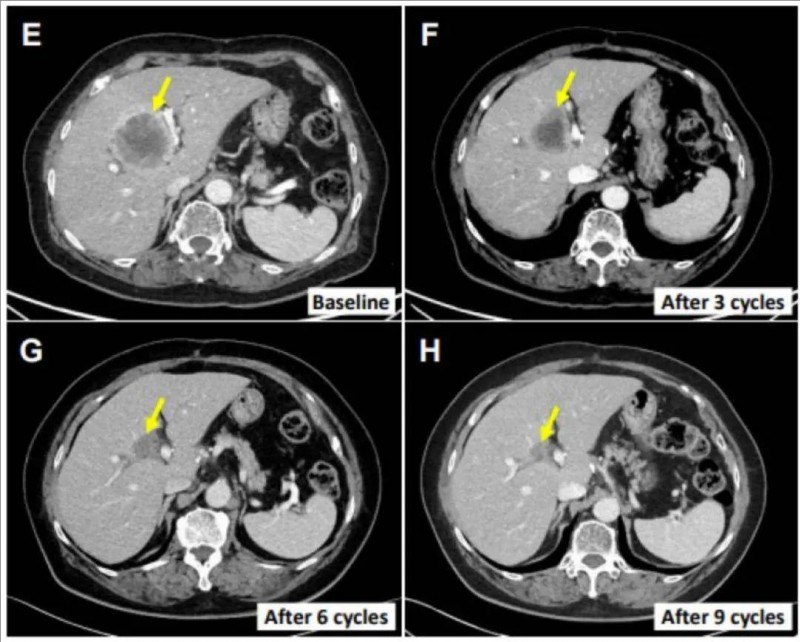

值得一提的是,其中一位患者表现出主要靶病变的持续客观消退,且在初始治疗后12个月病情无进展。该患者是一位76岁的肝外胆管癌女性患者(患者E0217),既往接受过胆总管节段切除术和胆囊切除术。但手术4个月后,发现多处肝转移。随后接受吉西他滨和顺铂全身化疗,然而效果依然不理想,多处肝脏病变随后进展。遂入组接受SMT-NK细胞+帕博利珠单抗治疗,令人惊喜的是,SMT-NK细胞+帕博利珠单抗联合治疗后,她的肝转移病变减少了70.4%(详见下图E-H),并且在初始治疗后12个月无进展。

▼E0217号患者在接受SMT-NK细胞治疗前后,主要肝转移病变CT图像对比

▲图源“Cancers (basel)”,版权归原作者所有,如无意中侵犯了知识产权,请联系我们删除

注:黄色箭头表示目标病变。每三个周期后进行一次反应评估。